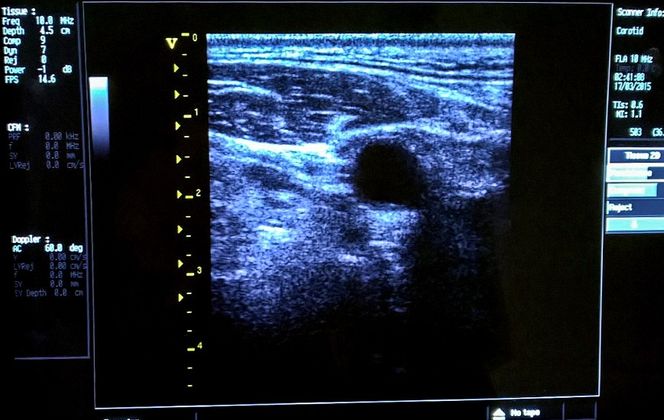

I væske, typisk i vann og i kroppen, er det snakk om høyere frekvenser som luft ikke er i stand til å bære. Her er området opp til 500 kHz i bruk i undervannsakustikk og fra 2 til 10 MHz for medisinsk ultralyd.

Men for ørsmå sensorer som dyttes inn i blodårer, og bare skal se noen mm forover kan det brukes opp til 50 MHz.

Når vi kommer inn i frekvenser som bare kan brukes i vann eller i kroppen øker bølgelengden. Ved 1,5 MHz er den 1 mm og ved 15 MHz er den 0,1 mm.

De ble spesialister på å utnytte ultralyd og dopplereffekten for å visualisere bevegelser, slik som blod. Ved se på hvordan frekvensen på det reflekterte signalet endret seg kan hastigheten til bevegelsene beregnes.